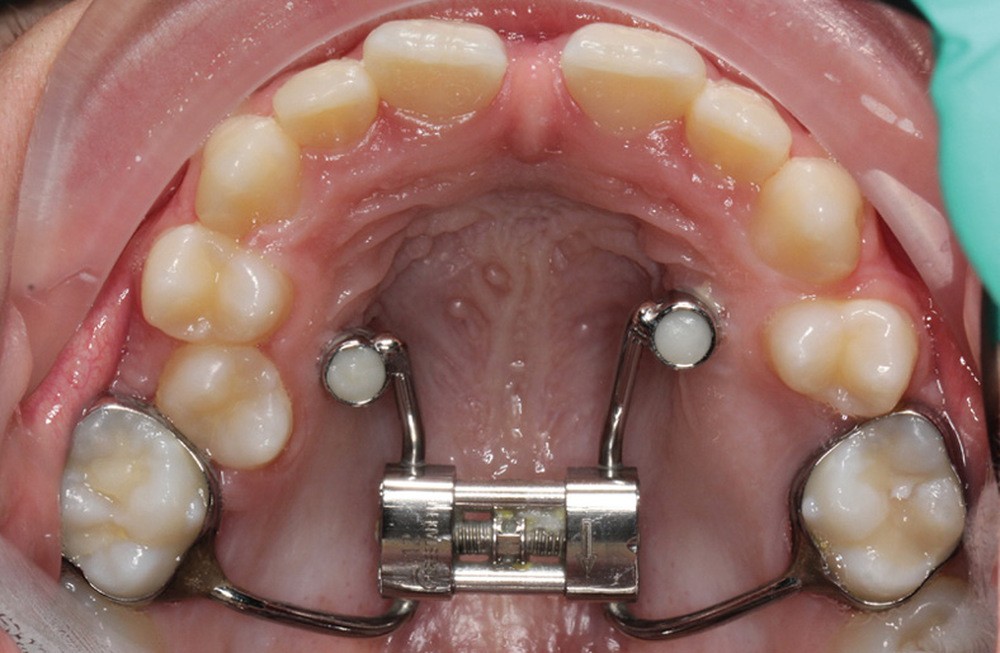

La matinée s’achèvera par le traitement de la dysharmonie dent-arcade par des techniques chirurgicales originales et novatrices : l’expansion transversale maxillo-mandibulaire (Dr Jean-Luc Ouhioun, fig. 2a-h) et la distraction sagittale du bloc incisivo-canin « front-block de Triaca » (Dr Olivier Esnault).

À côté de la coopération moindre qu’ils exigent, les ancrages squelettiques présentent également l’avantage de répondre à des indications très variées : correction des sourires gingivaux (Dr Skander Ellouze, fig. 3a-c), distalisation ou mésialisation molaire, supports pour les masques faciaux, mini transpalatin sur vis après expansion, ressorts de rétraction pour mettre en place les canines incluses sans léser les racines des dents adjacentes [3] (Dr Stéphane Renger, fig. 4) ou appareils d’expansion maxillaire (Dr Hans Winsauer, Dr Guido Sampersmans, fig. 5a-c)…